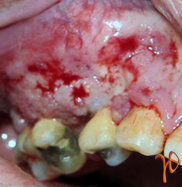

Στην κλινική εξέταση, ο ασθενής εξωστοματικά εμφάνιζε σκληρή ανώδυνη διόγκωση της παρειάς με εξάλειψη της ρινοχειλικής αύλακας(Εικ. 3) και ενδοστοματικά έφερε ανώδυνη συμπαγή και μαλακή μάζα με κοκκιώδη επιφάνεια η οποία καταλάμβανε τα ούλα και την ουλοπαρειακή αύλακα από την περιοχή του κυνόδοντα μέχρι και τον δεύτερο γομφίο(Εικ. 4).

Εικόνα 4. Βλάβη των ούλων εκτεινόμενη στην ουλοπαρειακή αύλακα.